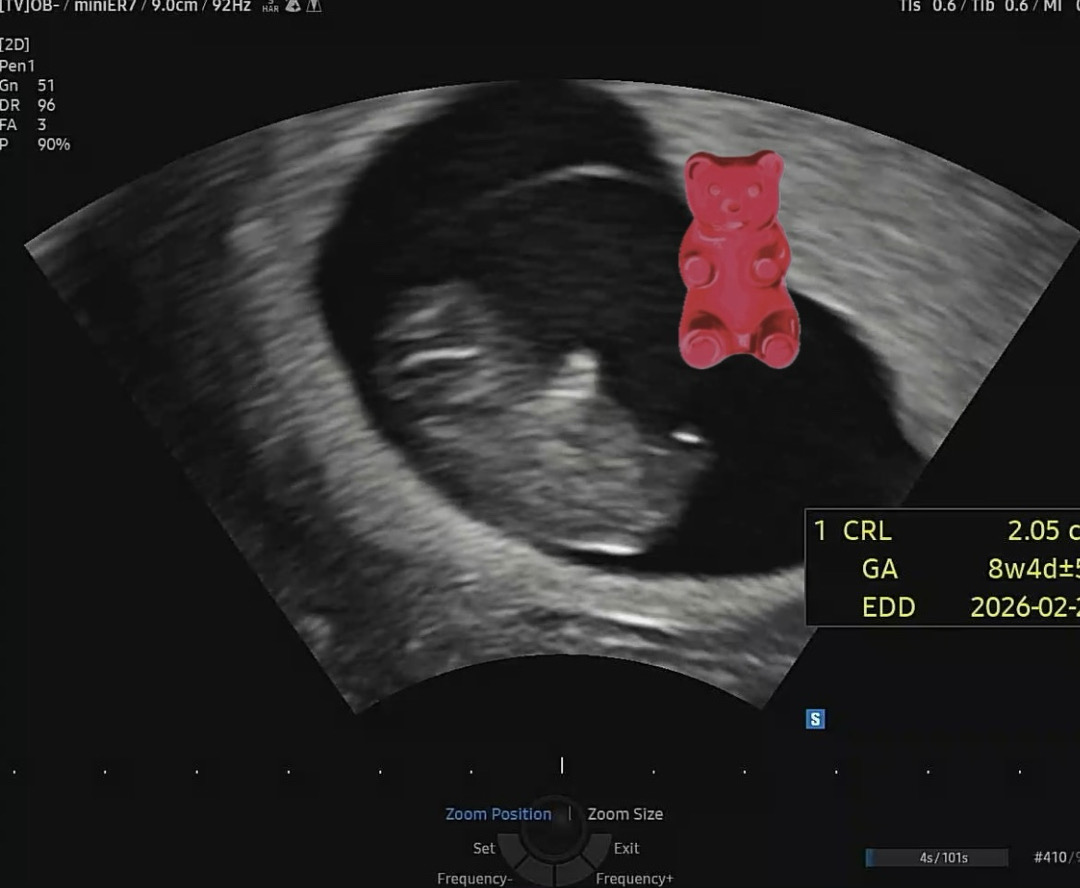

저두...💕 최고 귀여워용 젤리곰 시기🐻

9주 젤리곰보구왔어요 🤍

9주0일 꼬물꼬물 잘 놀고~ 무럭무럭 잘 크고 있는 조랑이입니다🐴🤍 젤리곰같이 너무 귀여워여 ...🫶